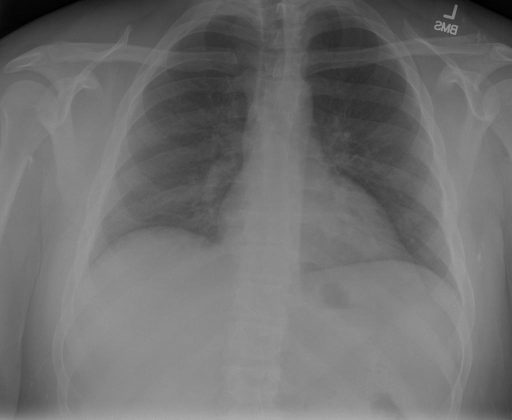

## 本文贡献  - 借助ChatGPT以及公开的数据集,我们构造了一个`X光影像-诊断报告`对的医学多模态数据集; - 我们将构建的中文胸部X光片诊断数据集在[VisualGLM-6B](https://github.com/THUDM/VisualGLM-6B)进行微调训练,并开放了部分训练权重用于学术研究; ## 数据集 - [MIMIC-CXR](https://physionet.org/content/mimic-cxr-jpg/2.0.0/)是一个公开可用的胸部X光片数据集,包括377,110张图像和227,827个相关报告。 - [OpenI](https://openi.nlm.nih.gov/faq#collection)是一个来自印第安纳大学医院的胸部X光片数据集,包括6,459张图像和3,955个报告。 在上述工作中,报告信息都为非结构化的,不利于科学研究。为了生成合理的医学报告,我们对两个数据集进行了预处理,并最终得到了可以用于训练的**英文报告**。除此之外,为了更好的支持中文社区发展,借助ChatGPT的能力,我们将英文报告进行了中文翻译,并最终形成了可用于训练的数据集。 |数据集|数量|下载链接| |:-|:-|:-| |MIMIC-CXR-zh|-|-| |OpenI-zh|6,423|[诊疗报告](./data/Xray/openi-zh.json) 、[X光影像](https://pan.baidu.com/s/13GBsDMKf6xBZBSHpoWH_EA?pwd=k9sh)| ## 快速上手 1. 安装环境 ```bash # 安装依赖 pip install -r requirements.txt # 国内换源安装依赖 pip install -i https://mirrors.aliyun.com/pypi/simple/ -r requirements.txt ``` 此时默认会安装`deepspeed`库(支持`sat`库训练),此库对于模型推理并非必要,同时部分`Windows`环境安装此库时会遇到问题。 如果想绕过`deepspeed`安装,我们可以将命令改为: ```bash # 安装依赖 pip install -i https://mirrors.aliyun.com/pypi/simple/ -r requirements_wo_ds.txt # 安装SwissArmyTransformer pip install -i https://mirrors.aliyun.com/pypi/simple/ --no-deps "SwissArmyTransformer>=0.3.6" ``` 2. 模型推理 CLI推理: ```python python cli_demo.py --from_pretrained checkpoints/finetune-XrayGLM-05-25-01-04 --prompt_zh '详细描述这张胸部X光片的诊断结果' ``` 更多[参数](https://github.com/WangRongsheng/XrayGLM/blob/main/cli_demo.py#L16) ## 效果展示 影像诊断: |X光影像|诊疗报告(医生)|XrayGLM| |:-|:-|:-| ||根据X射线图像,心脏大小正常,肺部看起来很清晰。已经排除了肺炎、积液、水肿、气胸、腺病、结节或肿块的存在。该发现表明一切正常。换句话说,总体印象是胸部正常。|X光片显示,心脏大小正常。肺部没有气胸或胸腔积液的证据。骨骼结构看起来没有任何异常。总的来说,X光片表明没有发现急性心肺疾病的迹象。| ||X光图片显示没有扭曲的区域、可疑的骨质不透明度或胸腺积液。心脏大小轻微增大,但非常稳定。此外,没有气胸的证据,肺野也正常。总体来说,X光片显示没有急性心脏异常,但要注意轻微的心脏扩大。|X光片显示,心脏大小正常。肺部和纵隔轮廓清晰,没有气胸或胸腔积液的证据。骨骼结构完整,没有任何急性异常。| ||心影形态在正常范围内。没有急性骨质异常。有可能出现没有明显的吸水或肺实质状况的线索。没有大面积积液或气胸。有可能怀疑其有误吸或肺实质问题。为了确诊和治疗,可能需要进行适当的影像学随访。|心脏大小正常,肺部和纵隔轮廓清晰。没有急性异常或活动受限的证据。没有任何明显的气胸、胸腔积液或肺不张的迹象。此外,也没有发现任何局灶性骨质异常或其他急性疾病。| 多轮对话: |X光影像|诊疗报告(医生)| |:-|:-| ||右侧主动脉突出观察到。心脏大小正常。胸部未发现明显的肺气肿、胸膜积液或可疑的肺部病变。报告指出已知右侧主动脉情况正常。| ```bash >> X光影像路径:./data/Xray/861_1.png >> 用户:这是一张什么图? >> XrayGLM:这张图片显示的是一张肺部检查的X光片。 >> 用户:请描述这张胸部X光片的诊断结果 >> XrayGLM:心脏大小正常,肺部清晰。没有急性心肺疾病的证据。 >> 用户:是否存在肺气肿? >> XrayGLM:没有肺气肿。心脏大小正常,肺部清晰。没有发现急性心肺疾病的证据。 >> 用户:平时饮食该注意什么? >> XrayGLM:饮食应该健康,均衡。建议增加蛋白质的摄入量,因为蛋白质有助于维持肌肉和骨骼的健康。多食用蔬菜、水果、全谷物以及健康的脂肪来源如橄榄油、鱼类等可以帮助获得足够的维生素和矿物质。此外,避免过度饮酒或吸烟,这些习惯可能会对心脏健康产生负面影响。 ``` ## 项目致谢 1. [VisualGLM-6B](https://github.com/THUDM/VisualGLM-6B)为我们提供了基础的代码参考和实现; 2. [MiniGPT-4](https://github.com/Vision-CAIR/MiniGPT-4)为我们这个项目提供了研发思路; 3. ChatGPT生成了高质量的中文版X光检查报告以支持XrayGLM训练; 4. [gpt_academic](https://github.com/binary-husky/gpt_academic)为文档翻译提供了多线程加速; 5. [MedCLIP](https://github.com/RyanWangZf/MedCLIP) 、[BLIP2](https://huggingface.co/docs/transformers/main/model_doc/blip-2) 、[XrayGPT](https://github.com/mbzuai-oryx/XrayGPT) 等工作也有重大的参考意义;  这项工作由[澳门理工大学应用科学学院](https://www.mpu.edu.mo/esca/zh/index.php)硕士生[王荣胜](https://github.com/WangRongsheng) 、[段耀菲](https://github.com/IsBaSO4) 、[李俊蓉](https://github.com/lijunrong0815)完成,指导老师为檀韬副教授、[彭祥佑](http://www.patrickpang.net/)老师。 *特别鸣谢:[USTC-PhD Yongle Luo](https://github.com/kaixindelele) 提供了有3000美金的OpenAI账号,帮助我们完成大量的X光报告翻译工作 ## 免责声明 本项目相关资源仅供学术研究之用,严禁用于商业用途。使用涉及第三方代码的部分时,请严格遵循相应的开源协议。模型生成的内容受模型计算、随机性和量化精度损失等因素影响,本项目无法对其准确性作出保证。即使本项目模型输出符合医学事实,也不能被用作实际医学诊断的依据。对于模型输出的任何内容,本项目不承担任何法律责任,亦不对因使用相关资源和输出结果而可能产生的任何损失承担责任。 ## 项目引用 如果你使用了本项目的模型,数据或者代码,请声明引用: ```bash @misc{wang2023XrayGLM, title={XrayGLM: The first Chinese Medical Multimodal Model that Chest Radiographs Summarization}, author={Rongsheng Wang, Yaofei Duan, Junrong Li, Patrick Pang and Tao Tan}, year={2023}, publisher = {GitHub}, journal = {GitHub repository}, howpublished = {\url{https://github.com/WangRongsheng/XrayGLM}}, } ``` ## 使用许可 此存储库遵循[CC BY-NC-SA](https://creativecommons.org/licenses/by-nc-sa/4.0/) ,请参阅许可条款。